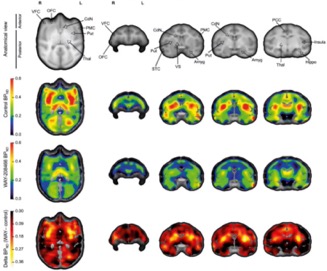

β SB-258585 reduces food motivation while blocking 5-HT6 receptors in the non-human primate striatum

M. Pitoy, L. Gauthier, J. Debatisse, J. Maulavé, E. Météreau, M. Beaudoin, K. Portier, V. Sgambato, T. Billard, L. Zimmer, S. Lancelot, L. Tremblay

Prog. Neuro-Psychopharmacol. Biol. Psychiatry 2024, 131, 110970